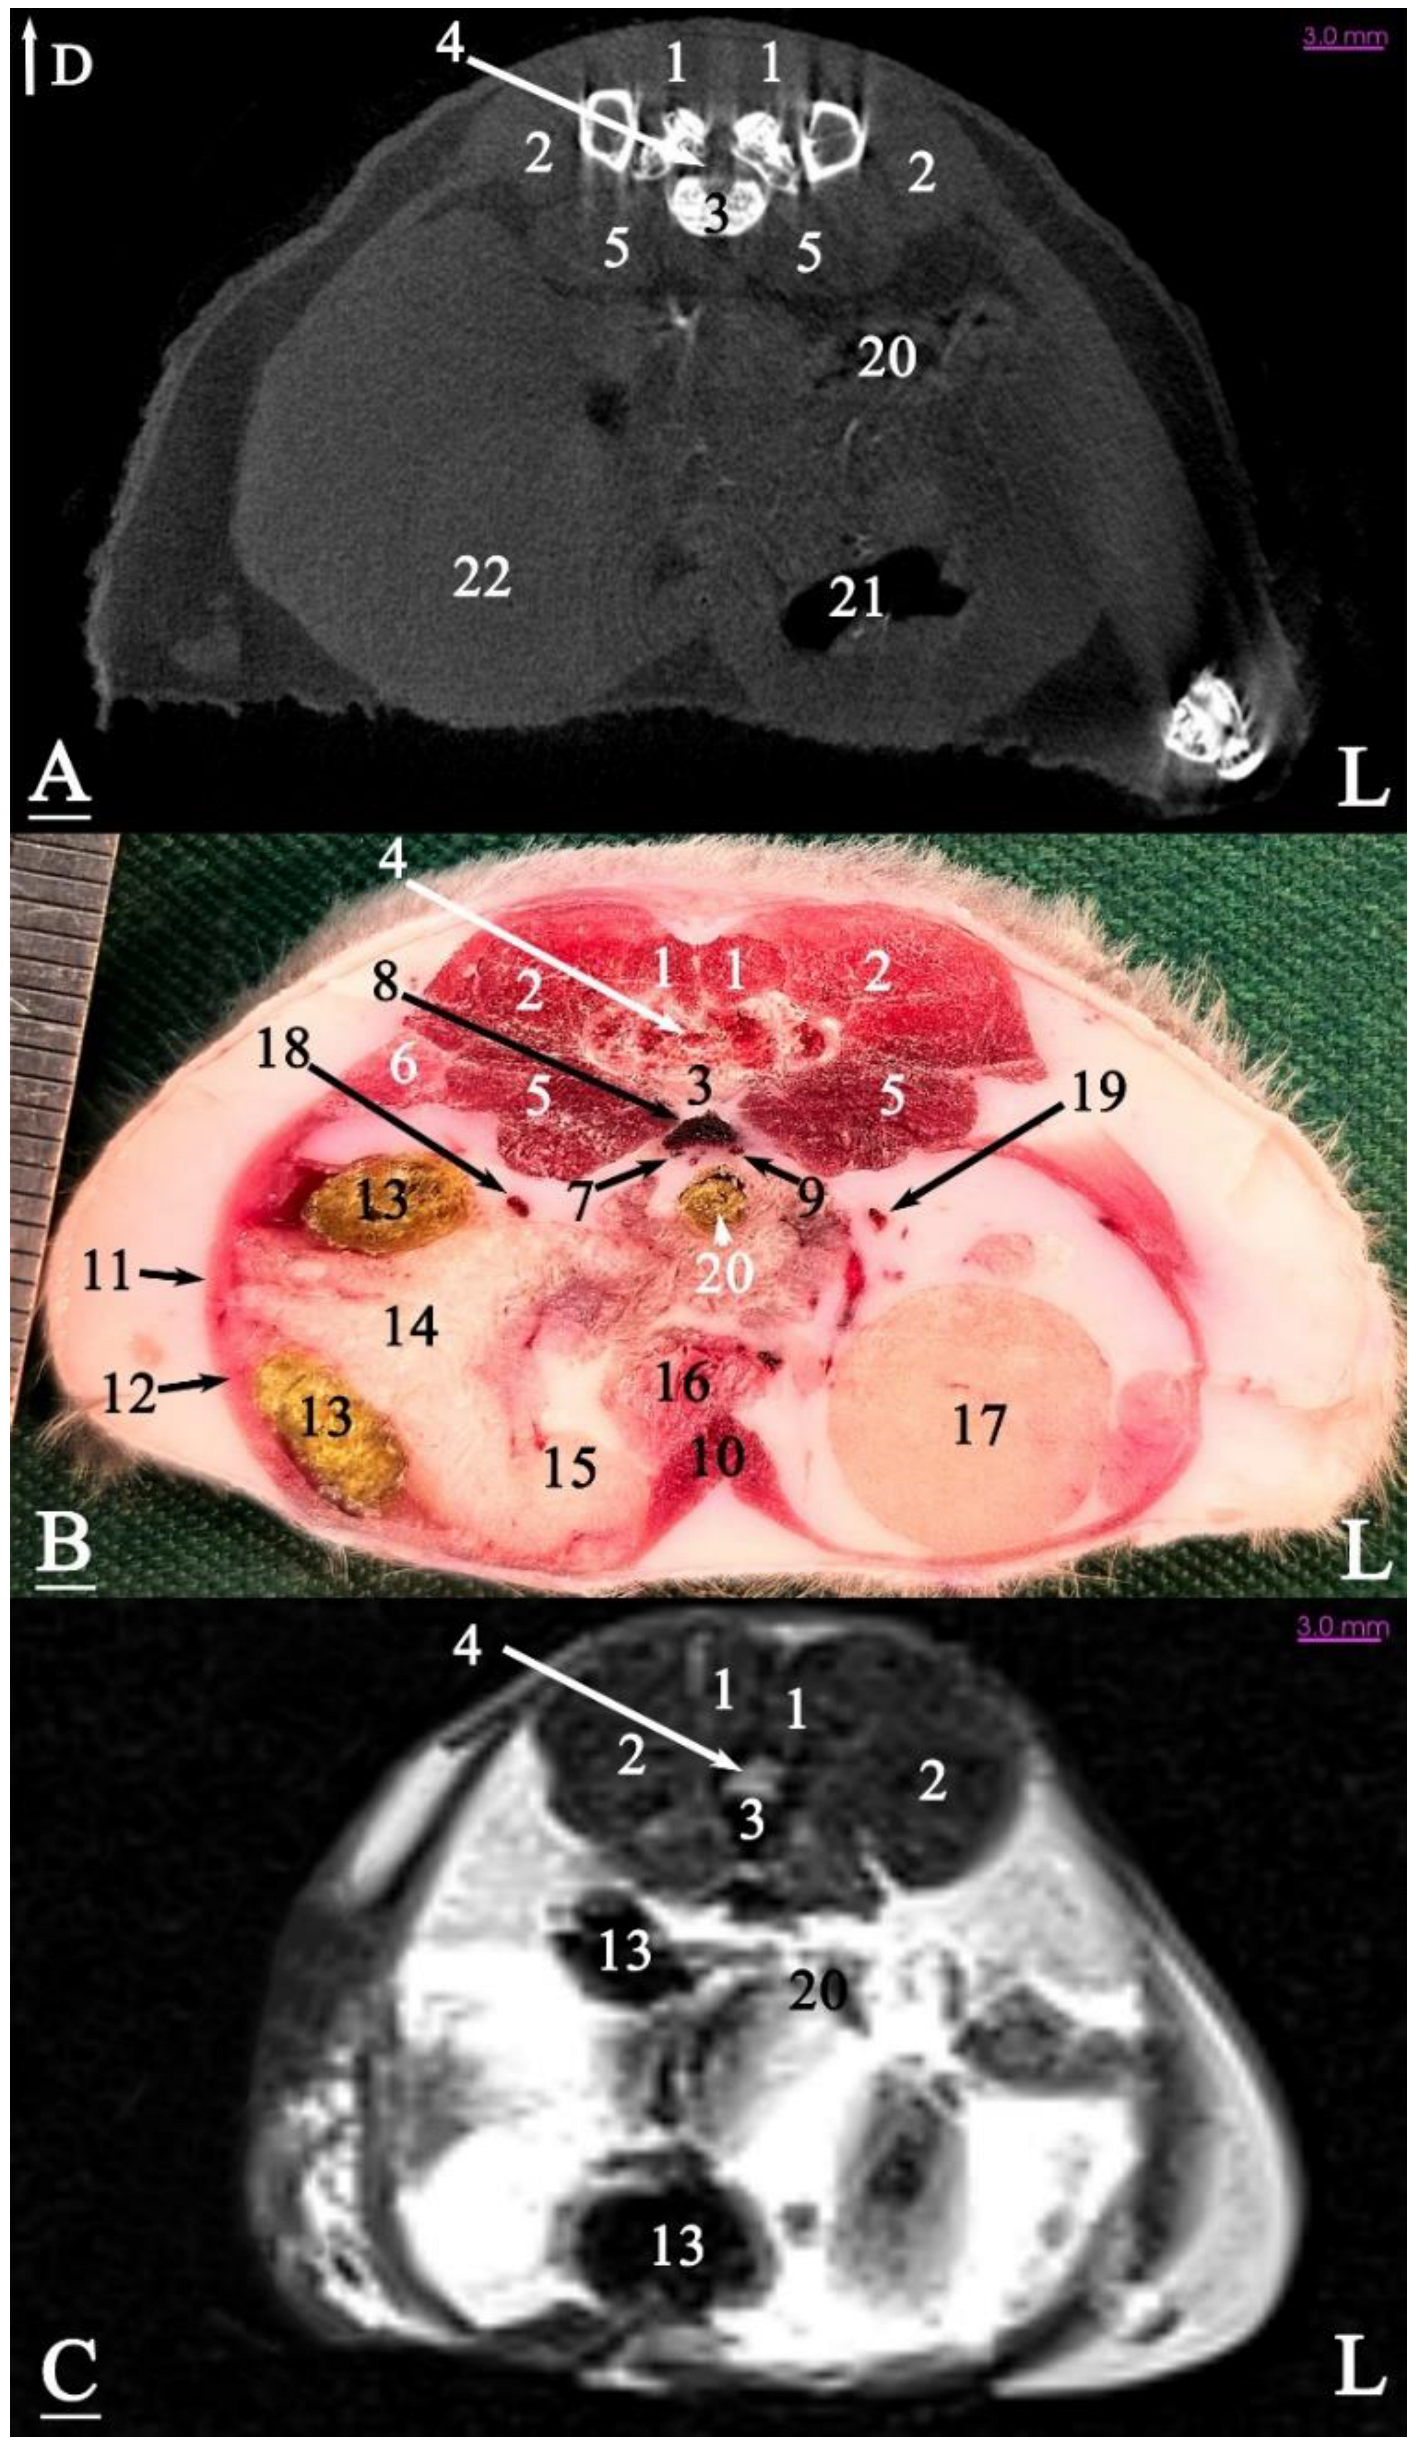

3.2.1. Transverse Cadaver Slices

3.3. Micro-CT Slices

3.4. MRI Slices